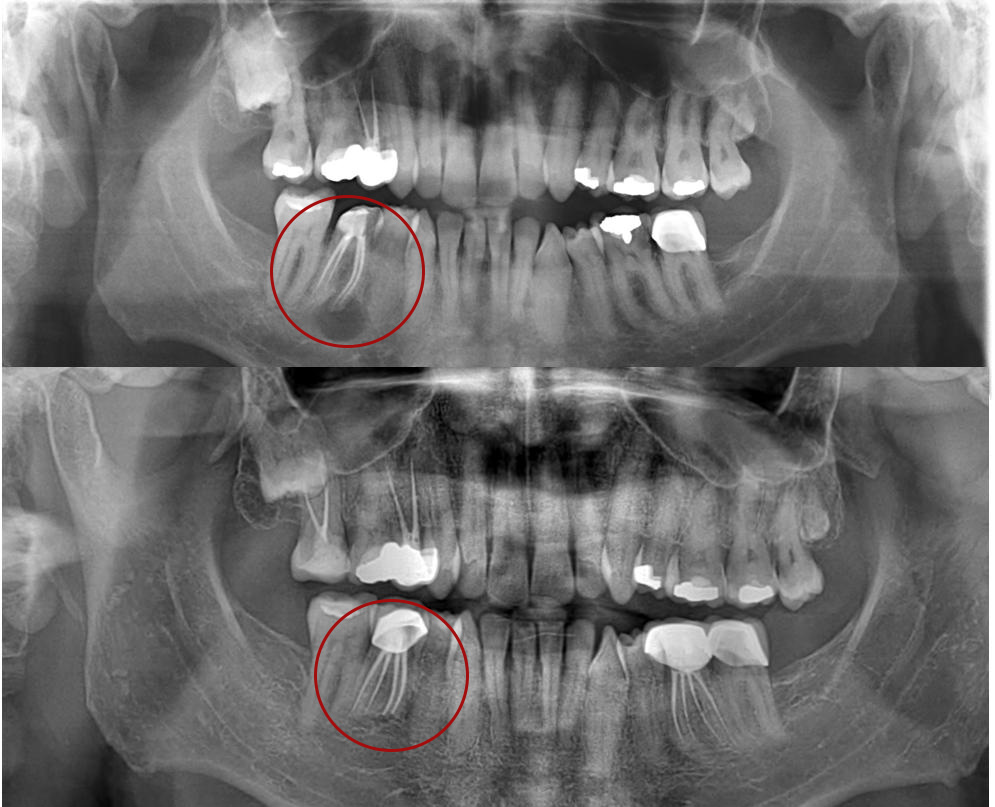

- Detaylı Muayene ve Röntgen

Öncelikle diş ve çevre dokular detaylı şekilde incelenir. Panoramik röntgen veya dental tomografi ile kistin boyutu ve konumu değerlendirilir.